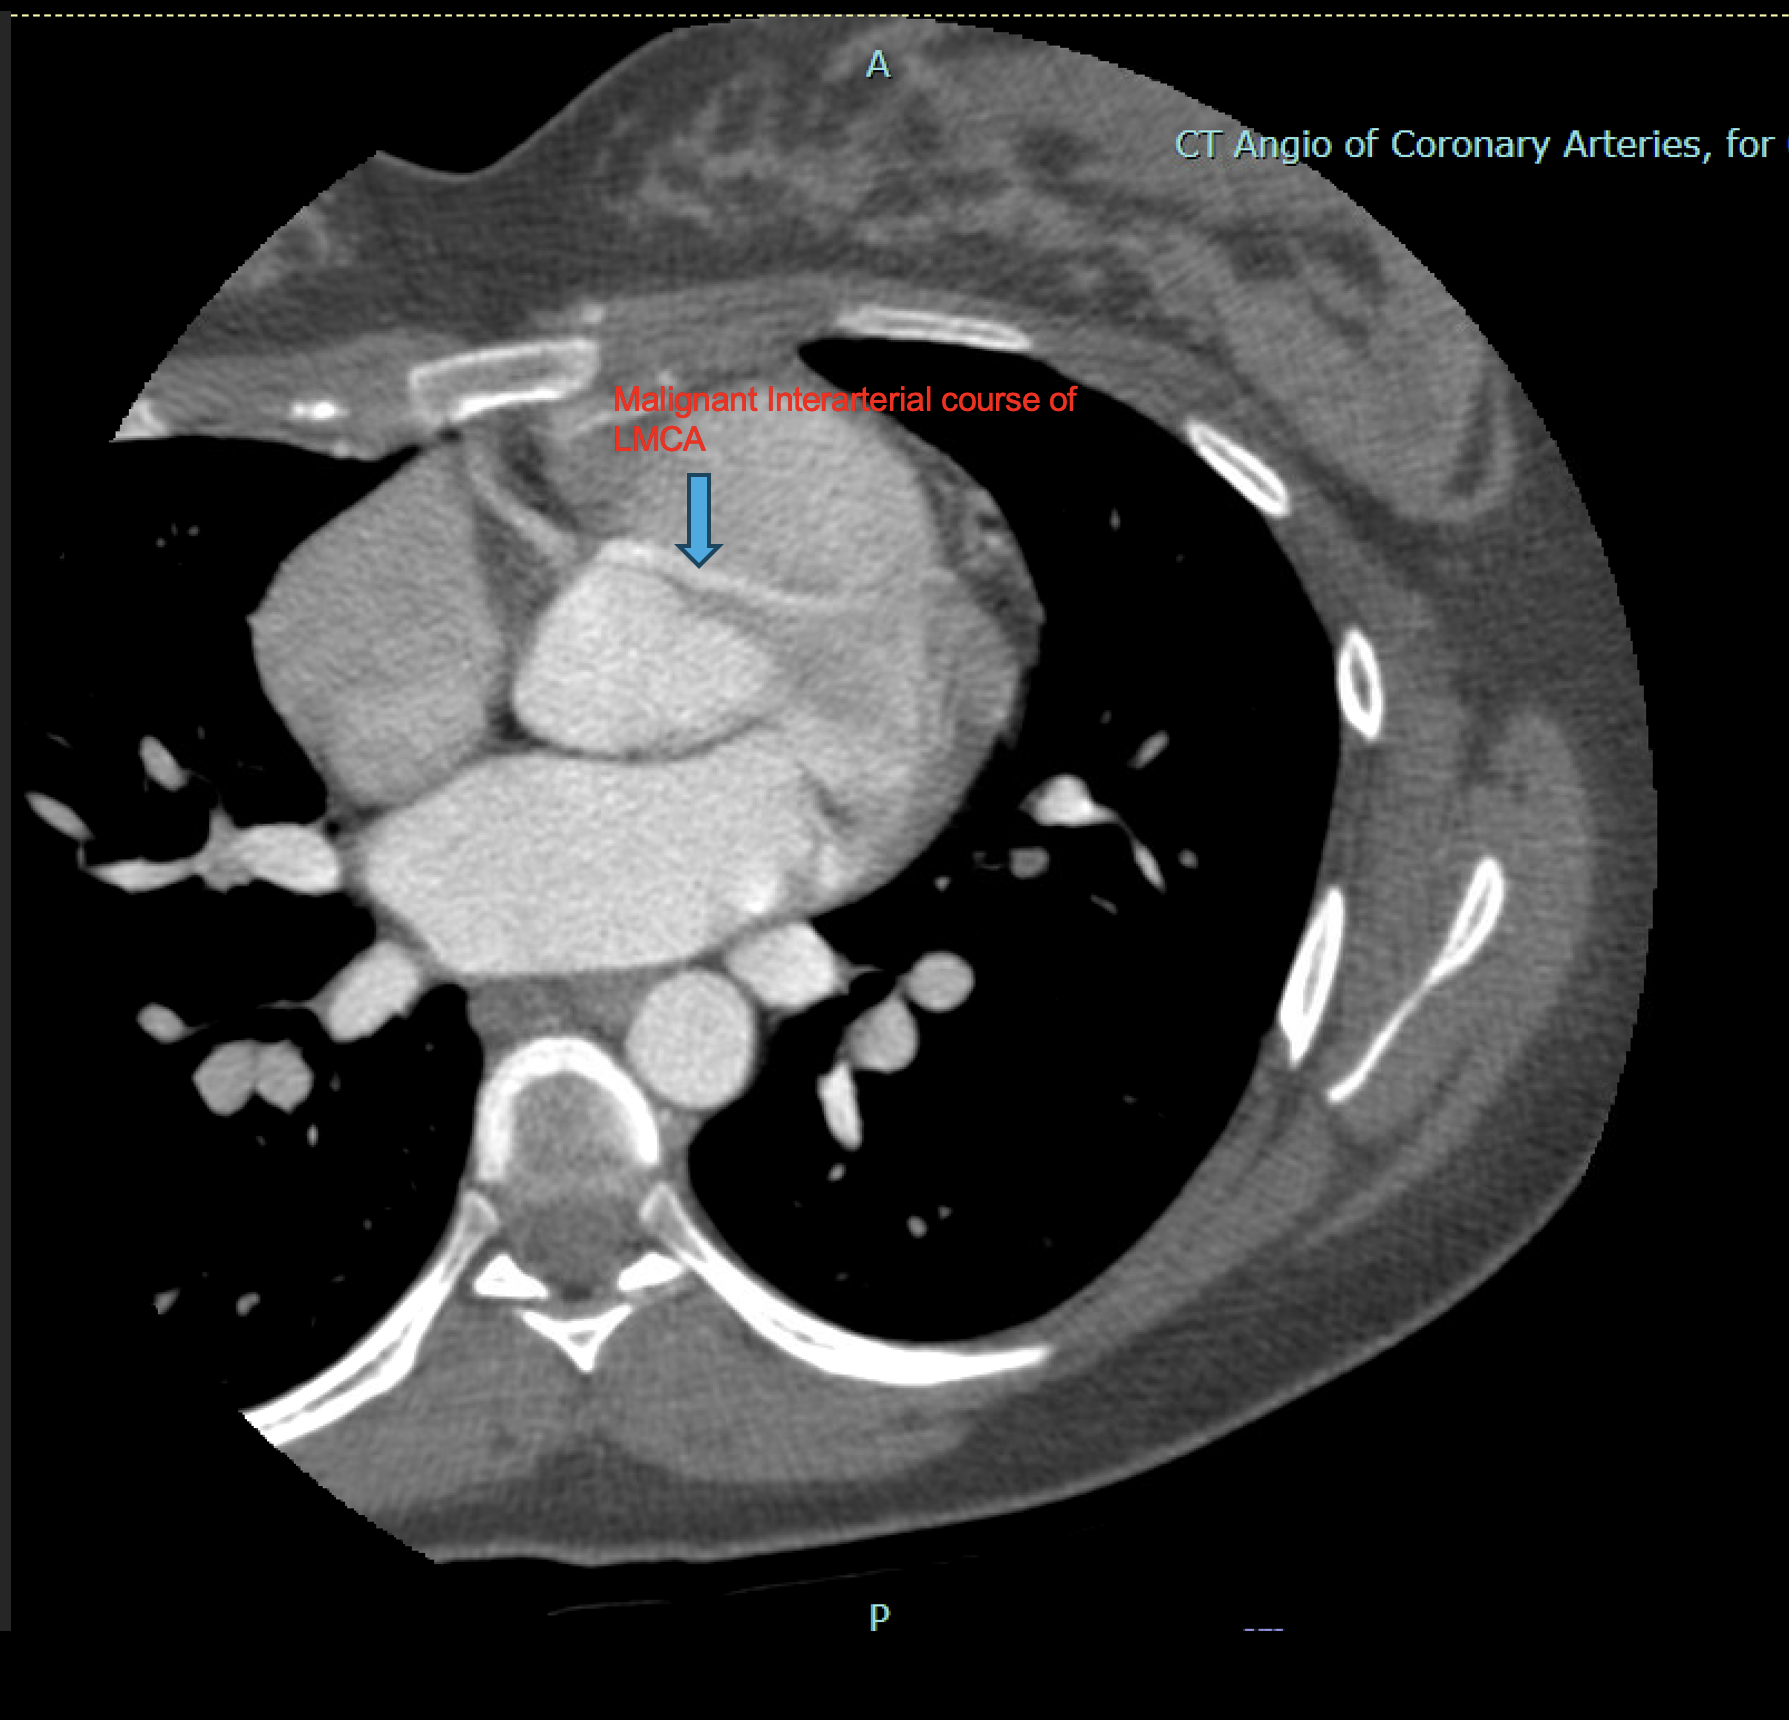

On presentation, vital signs were stable, and the acute coronary syndrome workup was negative. CT pulmonary angiography ruled out pulmonary embolism but revealed an anomalous left main coronary artery (LMCA) originating from the right coronary sinus and coursing between the aorta and pulmonary artery. She experienced intermittent chest pain and episodes of tachycardia up to 170 bpm, which were controlled with diltiazem.

Following an uncomplicated cesarean delivery at 39 weeks, coronary CTA and left heart catheterization were performed. These confirmed a malignant interarterial LMCA arising from a shared ostium with the right coronary artery. The artery had no obstructive lesions but demonstrated high-risk features, including an acute-angle takeoff and a possible slit-like ostium, prone to dynamic compression during exertion.

Coronary CTA is the preferred imaging modality for delineating coronary origin, course, and morphology. While Echo is widely used, its spatial resolution is limited. Cardiac MRI, traditional angiography, and intravascular ultrasound offer complementary data but may be limited by availability or invasiveness.